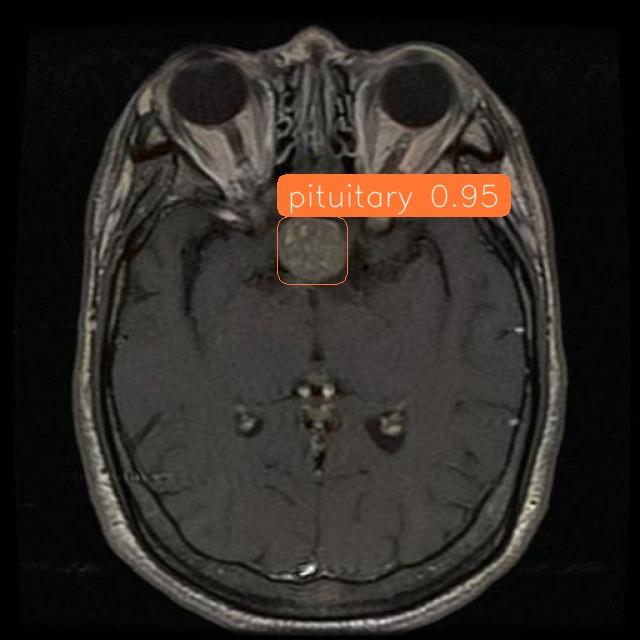

Fig 7: Image showing workflow results.

Below are the scan results:

ID: fdb02240-c9ed-41f8-abc4-ae68524bdf06

Prediction: PITUITARY

Confidence: 0.949749231338501 ~ 94%

Size: 47mm²

Morphology:

- The image displays an irregular, roughly circular shape with a blurred appearance.